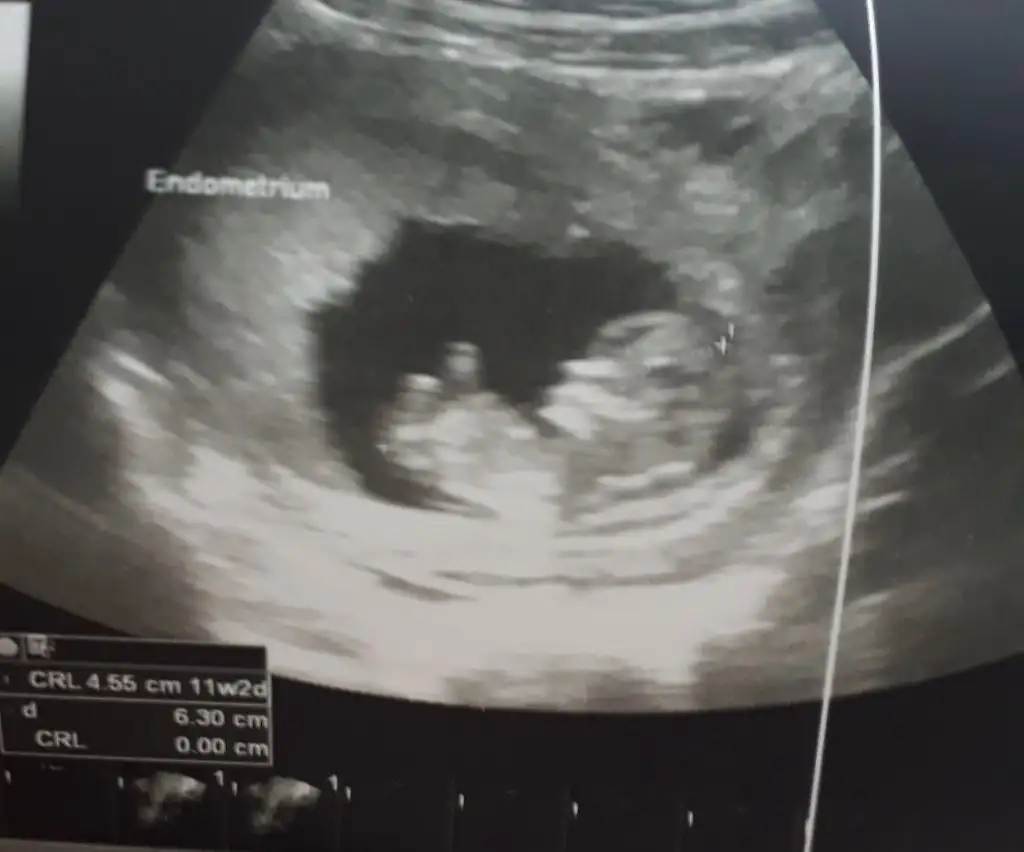

Erkek gibi duruyor hayırlı olsun diyelimMerhaba arkadaşlar cinsiyet tahmini yapabilen var mı aramızda

11+4 görüntüleri ekliyorum . Merakla bekliyorum yorumlarimizi ..

Kesen yuvarlak kız gibi duruyor öncelikle hayırlısı olsun inşallah sağlıkla ilerler gebeliğiniz umarım sorunsuz bir şekilde doğar evladınızŞunlar canım tam 12 haftalık çok teşekkür ederim